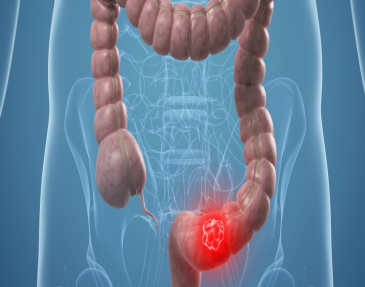

Colon

Los pacientes pueden presentar múltiples patologías en el Colon que requieren de manejo quirúrgico:

Cáncer

El cáncer de colon tiene actualmente una alta frecuencia y en estados avanzados tiene un pronóstico desfavorable, es por ello, que se requiere de un diagnóstico y tratamiento oportuno con la finalidad de obtener los mejores resultados quirúrgicos y la mayor sobrevida para el paciente. Es por ello que se ofrece un manejo integral mediante un diagnóstico temprano por Colonoscopía y manejo quirúrgico seguro, adecuado y oportuno para el paciente.